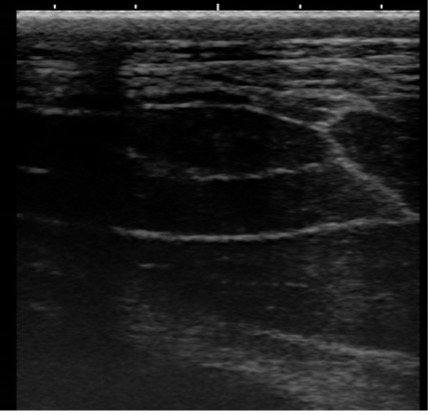

断面①

腎盂が拡張しています。右に示す他の牛と比較することでよくわかります。

断面②

通常であればエコーで映せないはずの尿管が内腔1cmまで拡張し、壁は肥厚しています。

以上の画像と触診から、腫瘤①が尿管を巻き込むように形成されており、巻き込まれた尿管は著しく狭窄し(③④)、腎盂および腫瘤より腎臓側の尿管は鬱滞した尿により著しく拡張している(①②)ことがわかりました。